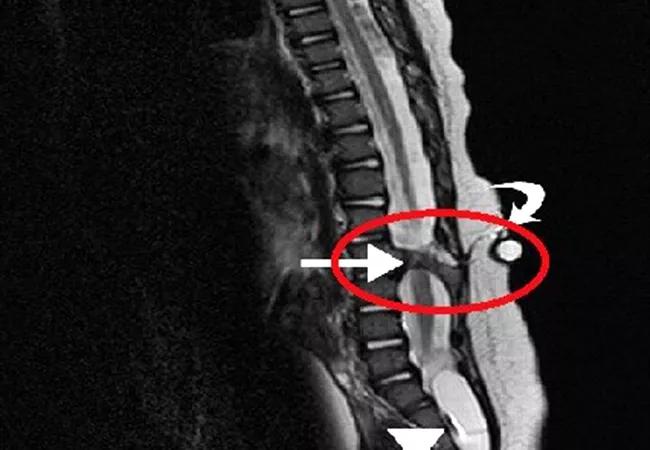

Myelomeningocele, also known as spina bifida, is one of many complex congenital defects involving the urological system. It is the most common permanent congenital anomaly in the United States. In developing countries, with less access to health care technologies, personnel and disposable resources (e.g., catheters, ostomy appliances), the challenges in caring for patients with these types of complex conditions are amplified. Cultural differences impact care for these patients and their opportunities for living a full adult life.